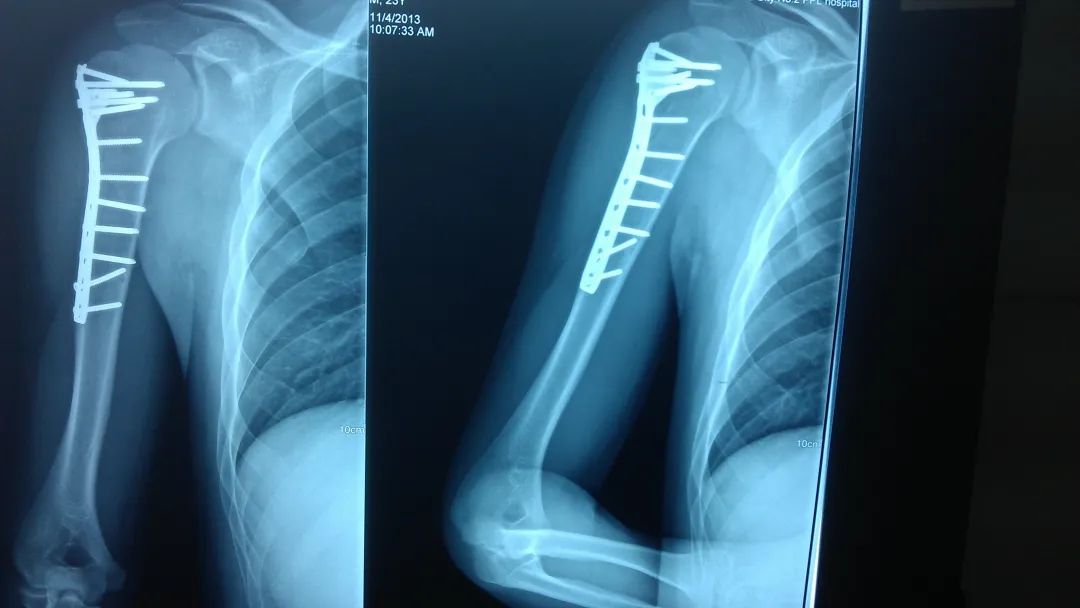

对于肱骨近端骨折如果没有移位,可以做肩关节悬吊固定,如果是明显移位的骨折或者是粉碎性骨折,也是需要做切开复位钛板螺钉内固定手术。每个人到了老年,都会出现骨密度降低,骨小梁变细,骨量减少,即俗称的骨质疏松症,在受到一定外力之后,很容易造成骨折。